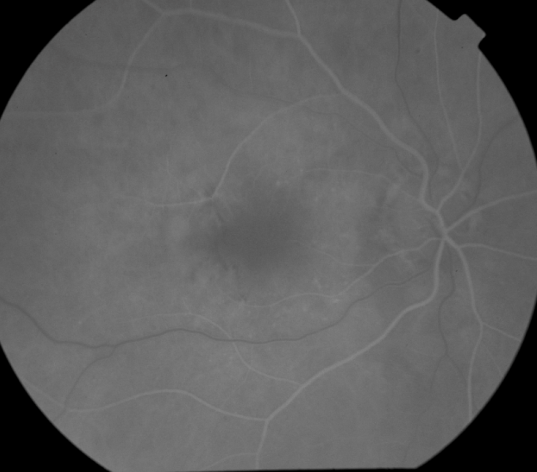

OD Red-Free: Pre-Injection: Arterial: A-V: Venous: Recirculation: Late:

OS Red-Free: Venous: Recirc: Late:

Impression